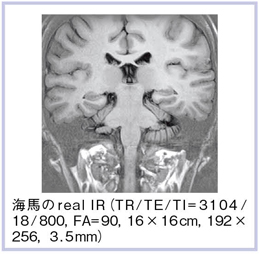

4)real IR

real IRは,薄いスライス厚でもコントラスト分解能に優れた撮像法である。痴呆性疾患などで注目されている海馬領域を中心に,T1強調の2Dスキャンを行った(図11)。画像を拡大すると,内部のコントラストも非常に良好なことがわかる(図12)。同様にT2強調の2D-STIRでも,比較的良好な画像が得られている(図13)。海馬内部の微細構造も,高い空間分解能で描出することが可能となっている。

![]() 図11 海馬領域のreal IR |

![]() 図12 図11の拡大画像 |